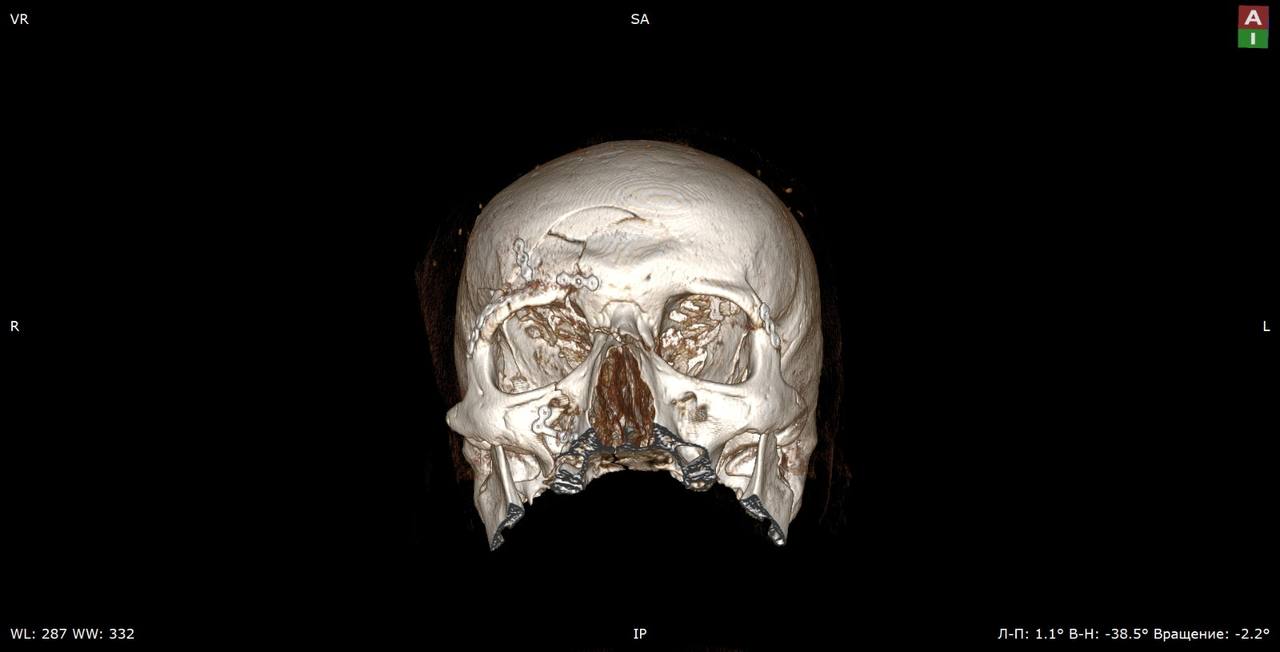

В отделение челюстно-лицевой хирургии ГБУЗ «Жуковская ОКБ» был экстренно доставлен 36-летний пациент, который упал с электросамоката и получил множественные переломы черепа — мозгового и лицевого отделов.

Как рассказали «Медицинской России» в больнице, среди полученных травм — переломы верхних, латеральных, нижних стенок глазниц, множественные переломы стенок верхнечелюстных пазух со смещением, правой скуловой дуги, ячеек решетчатой кости, верхней челюсти справа, крыловидных отростков клиновидной кости, ветвей нижней челюсти с двух сторон, тела нижней челюсти со смещением, лобной кости.

«Операция продолжалась более трех часов, в ходе нее врачам пришлось практически снять кожу головы, как скальп, зафиксировать все переломы специальными крепежами, а затем вернуть кожу на место, восстановив прежний облик», — рассказал хирург отделения челюстно-лицевой хирургии Тамаз Тотладзе.